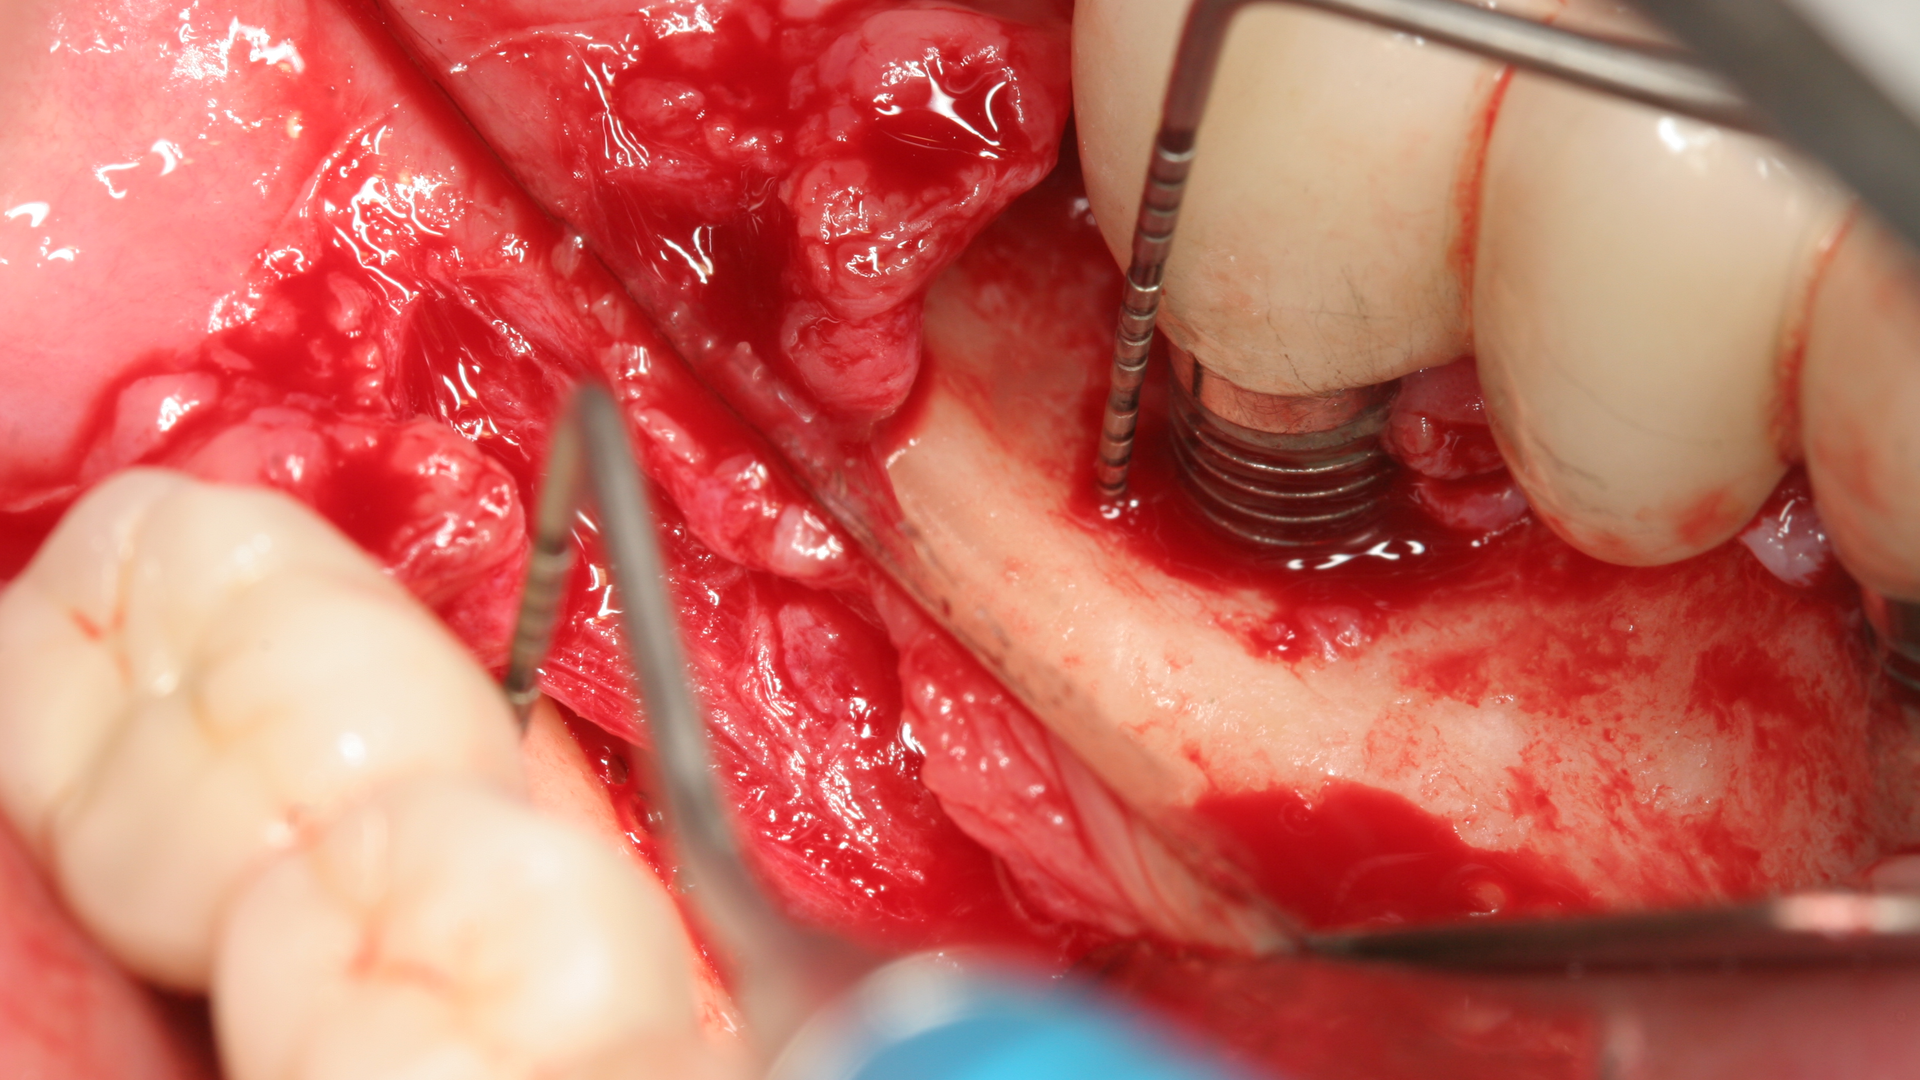

The expense and technical difficulty of removing an implant, rebuilding the defect, and replacing the failed dental implant with a new one can often be challenging. In addition, regenerative treatments for dental implant repair can be both costly and unpredictable if not done correctly (figures 1–3). Long-term maintenance and clinical oversight of peri-implant disease remains the most cost-effective and successful preventive measure for treating this disease.8 If this AI technology helps to determine the failure risk for the patient after surgical repair of the diseased dental implant, explantation with the replacement of a new implant or fixed/removable prosthesis may offer a better treatment alternative.